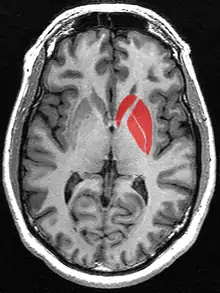

Striatum highlighted in green on coronal T1 MRI images

Striatum highlighted in green on sagittal T1 MRI images

Striatum highlighted in green on transversal T1 MRI images